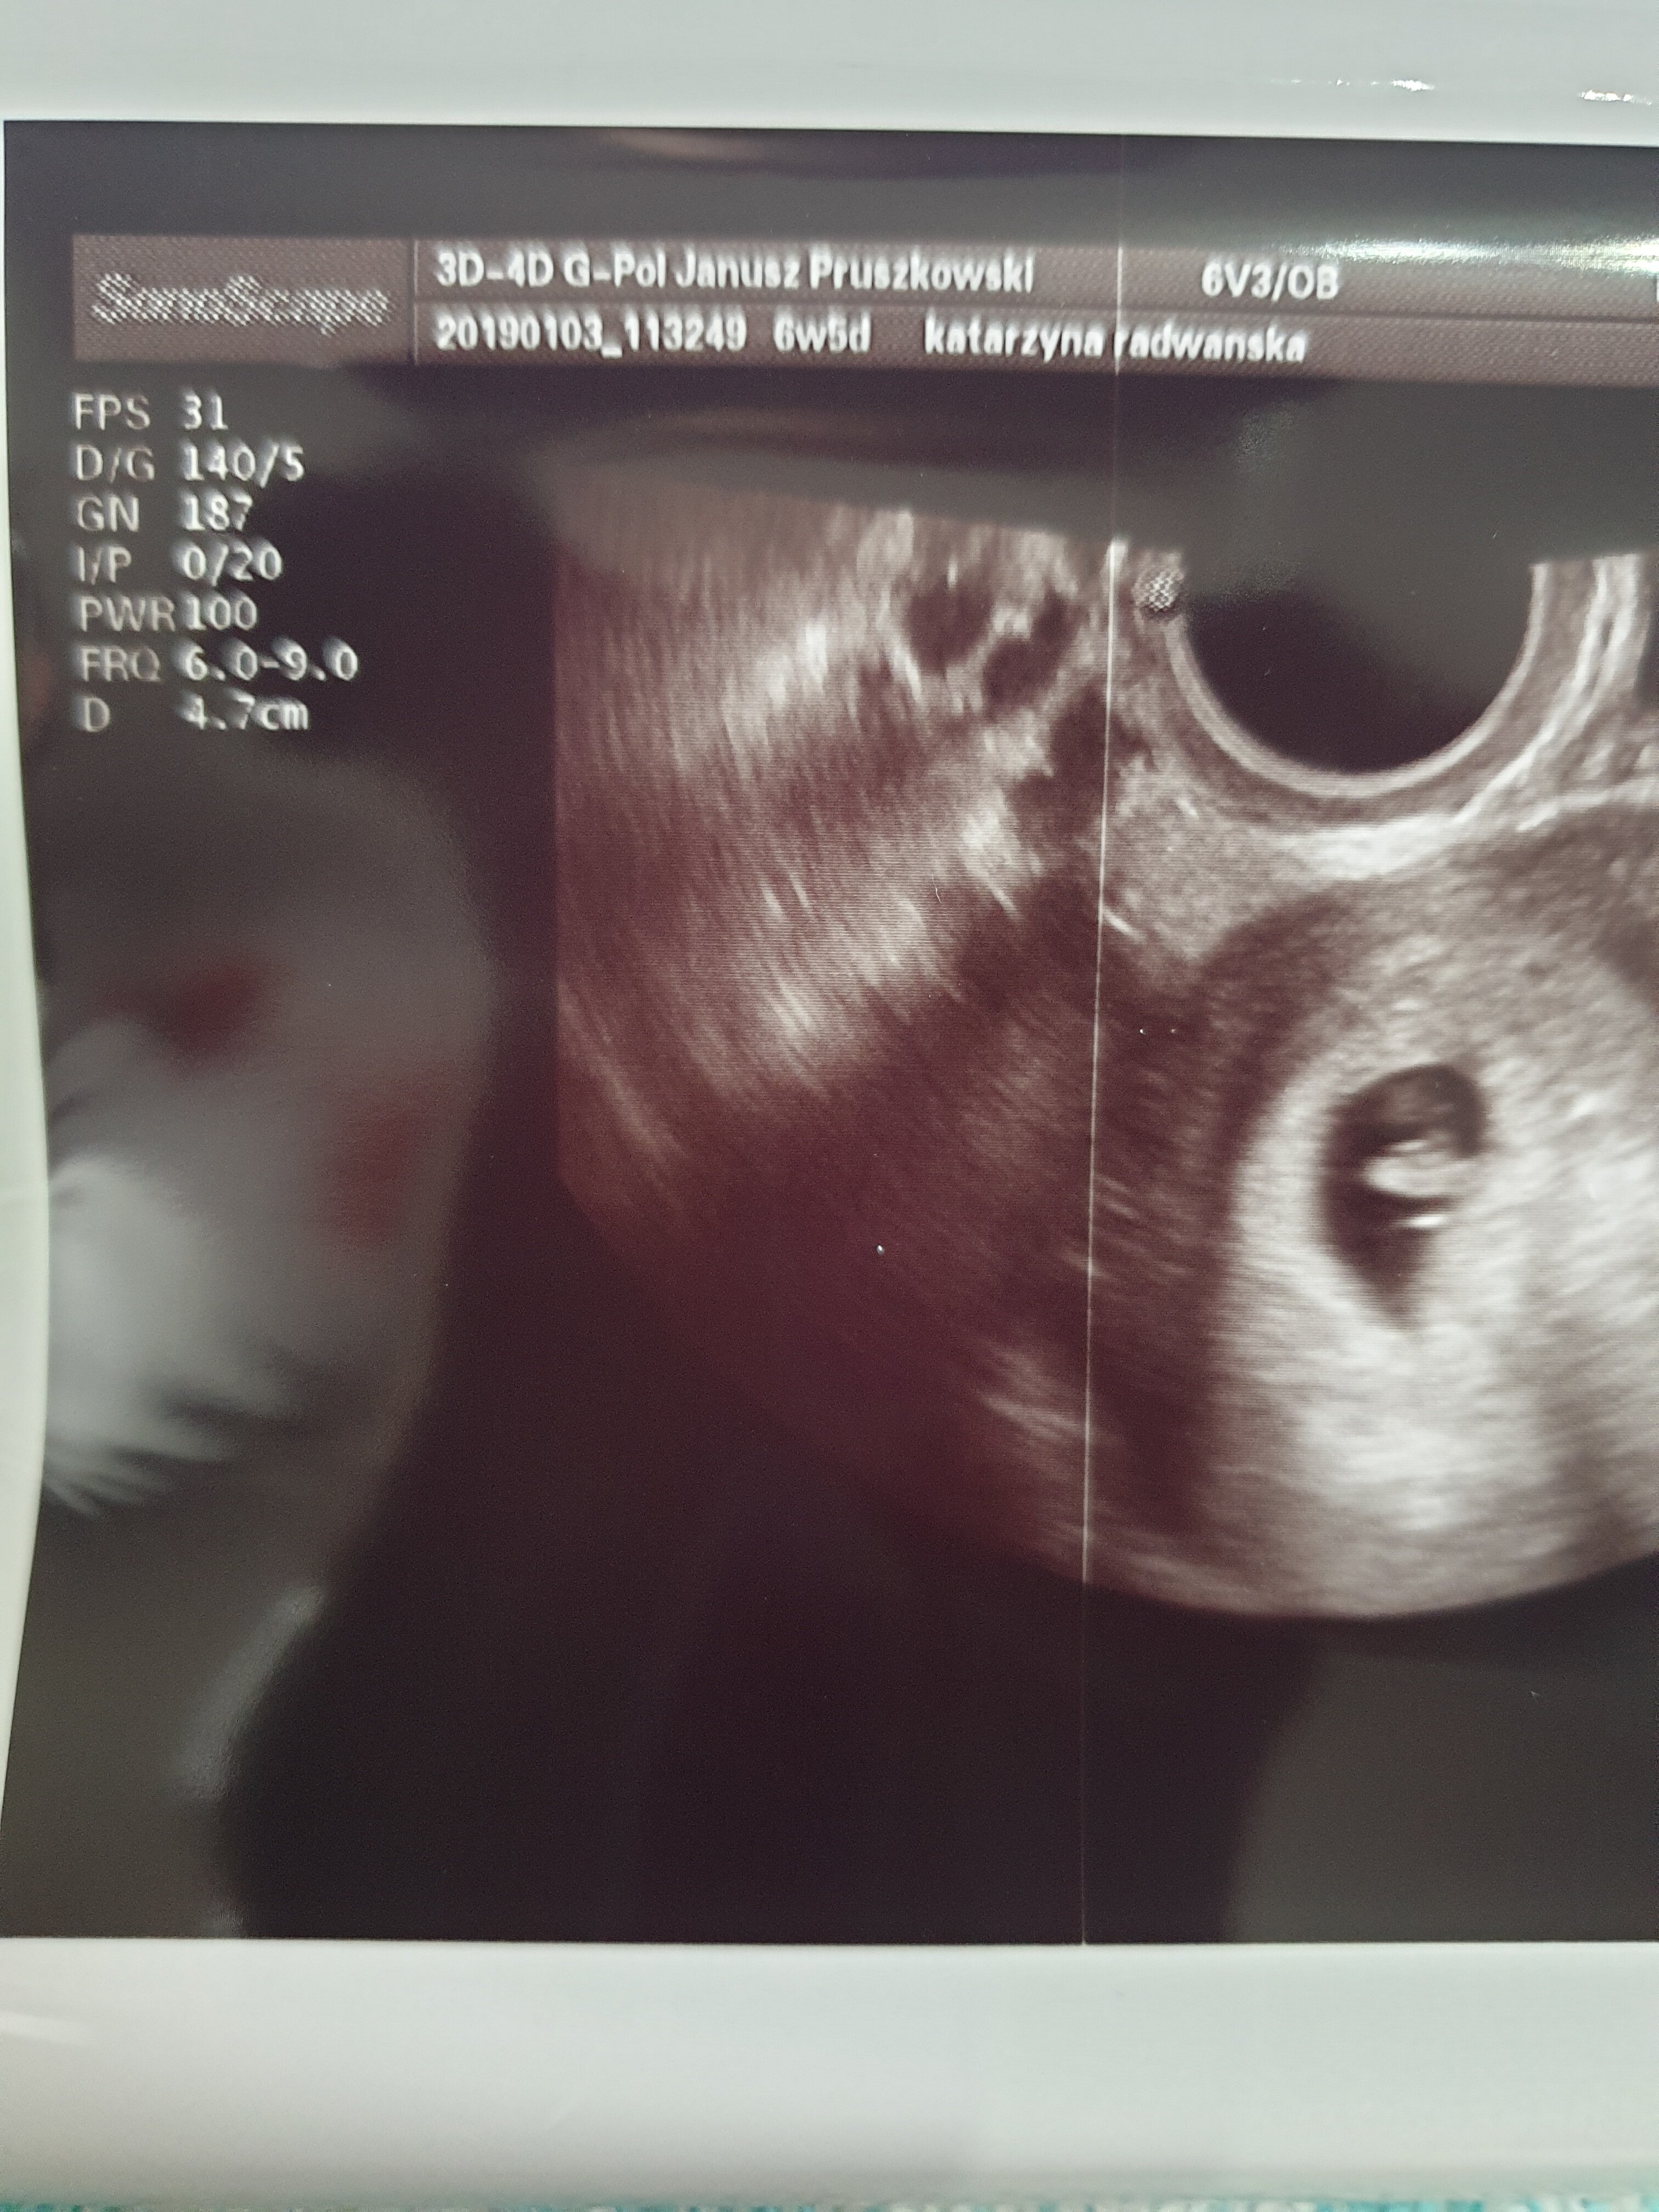

ładnie jak na 6 tydzień, ale kurczę jakie Ty masz mega dobek jakości zdjęcie usg ! Jestem w szokuCześć dziewczyny ja też dzisiaj po wizyciemoja fasolka ma 0,5 cm bije

wychodzi według USG 6t1dz